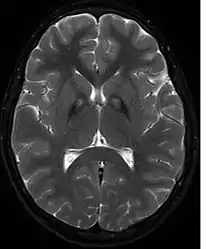

A neurological examination would show evidence of muscle rigidity; weakness; and abnormal postures, movements, and tremors. If other family members are also affected, this may help determine the diagnosis. Genetic tests can confirm an abnormal gene causing the disease. However, this test is not yet widely available. Other movement disorders and diseases must be ruled out. Individuals exhibiting any of the above listed symptoms are often tested using MRI (Magnetic Resonance Imaging) for a number of neuro-related disorders. An MRI usually shows iron deposits in the basal ganglia. Development of diagnostic criteria continues in the hope of further separating PKAN from other forms of neurodegenerative diseases featuring NBIA.

Microscopic features of PKAN include high levels of iron in the globus pallidus and the pars reticulata of substantia nigra, evident as a characteristic rust-brown discoloration[7] in a pattern called the eye-of-the-tiger sign;[8] lipofuscin and neuromelanin concentrated in the iron-accumulating areas; oval, nonnucleated structures representing swollen axons whose cytoplasm swells with vacuoles, referred to as spheroids, axon schollen, or neuroaxonal dystrophy; and Lewy bodies.[7]

Diagnosis of PKAN hit a milestone with the availability of MRIs, as well as the in-depth descriptions of those MRIs provided by Littrup and Gebarski (1985),[14] Tanfani et al. (1987),[15] Sethi et al. (1988),[16] Angelini et al. (1992),[17] Casteels et al. (1994),[18] and Malandrini et al. (1995).[19] The gene was localized to chromosome 20p by Taylor et al. (1996) [20] who suggested that this disorder should be referred to as neurodegeneration with brain iron accumulation (NBIA1) to avoid the objectionable eponym[21] of Hallervorden-Spatz. The disease was renamed 'pantothenate kinase-associated neurodegeneration' or PKAN by Zhou et al. (2001)[3] who suggested the name to avoid misinterpretation and to better reflect the true nature of the disorder. Most recently Pellecchia et al. (2005) published a report of 16 patients affected by PKAN, confirmed by genetic analysis.[22]